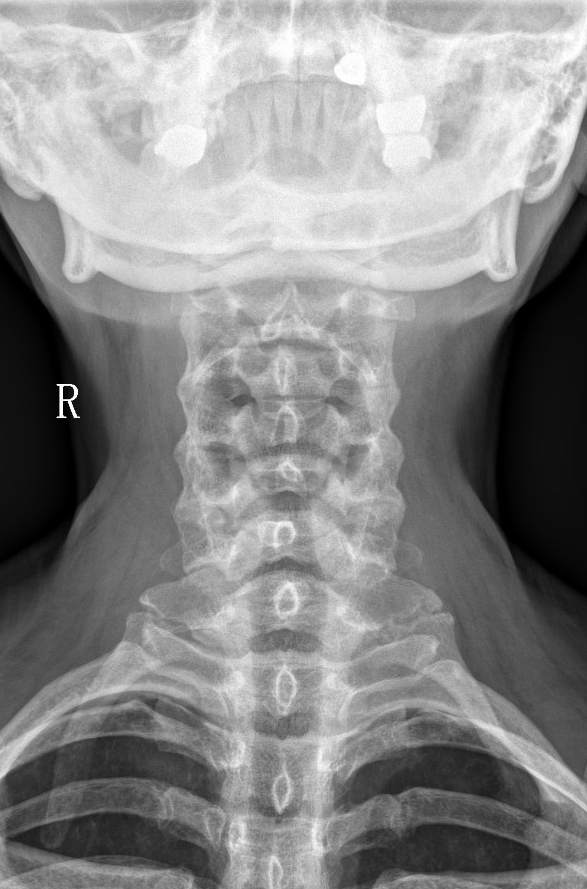

【影像】颈椎开口位X线片寰齿侧间隙不对称,枢椎棘突偏右。

本案以头晕、恶心、困倦、嗜睡为主症,没有颈部症状,症状诊断依据不充分。查体项僵、C2右侧横突后方压痛(+)、双侧上斜方肌、后斜角肌压痛(+),证实颈椎病的存在。旋颈试验(+)证实眩晕与颈椎存在相关性。开口位片寰齿侧间隙不对称、枢椎棘突偏右,证实寰枢关节错缝。综上印象诊断为“颈源性眩晕”。